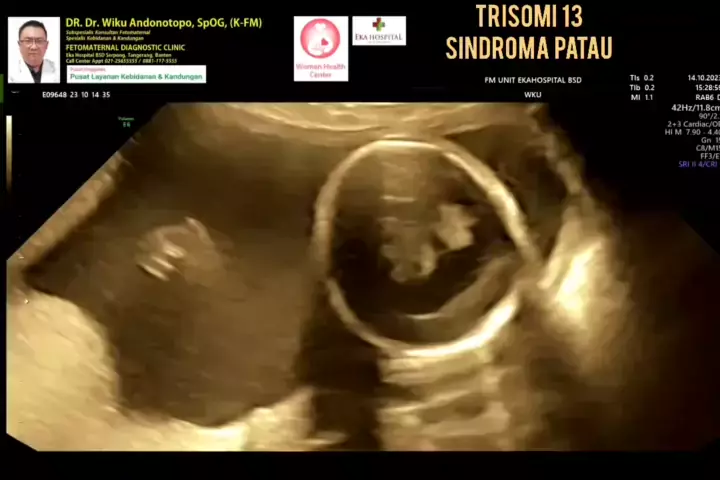

Sindroma Patau (Trisomia 13).... #skriningkehamilan #drwikuandonotopo #drwiku_andonotopo #polikandunganekahospitalbsd #ekahospitalbsd #ekahospitalcibubur #ekahospitalpekanbaru #ekahospitalbekasi #rsiafamilypluit #grandfamilypik #usgkehamilansehat #usgkehamilan #usg4d #usg4dimensi #fetomaternal #usgfetomaternal #konsultanfetomaternal #fetomaternalpontianak #fetomaternalekahospitalbsd #fetomaternaljakarta #fetomaternalserpong #fetomaternaltangerang #fetomaternalmedan #fetomaternalpalembang #fetom...